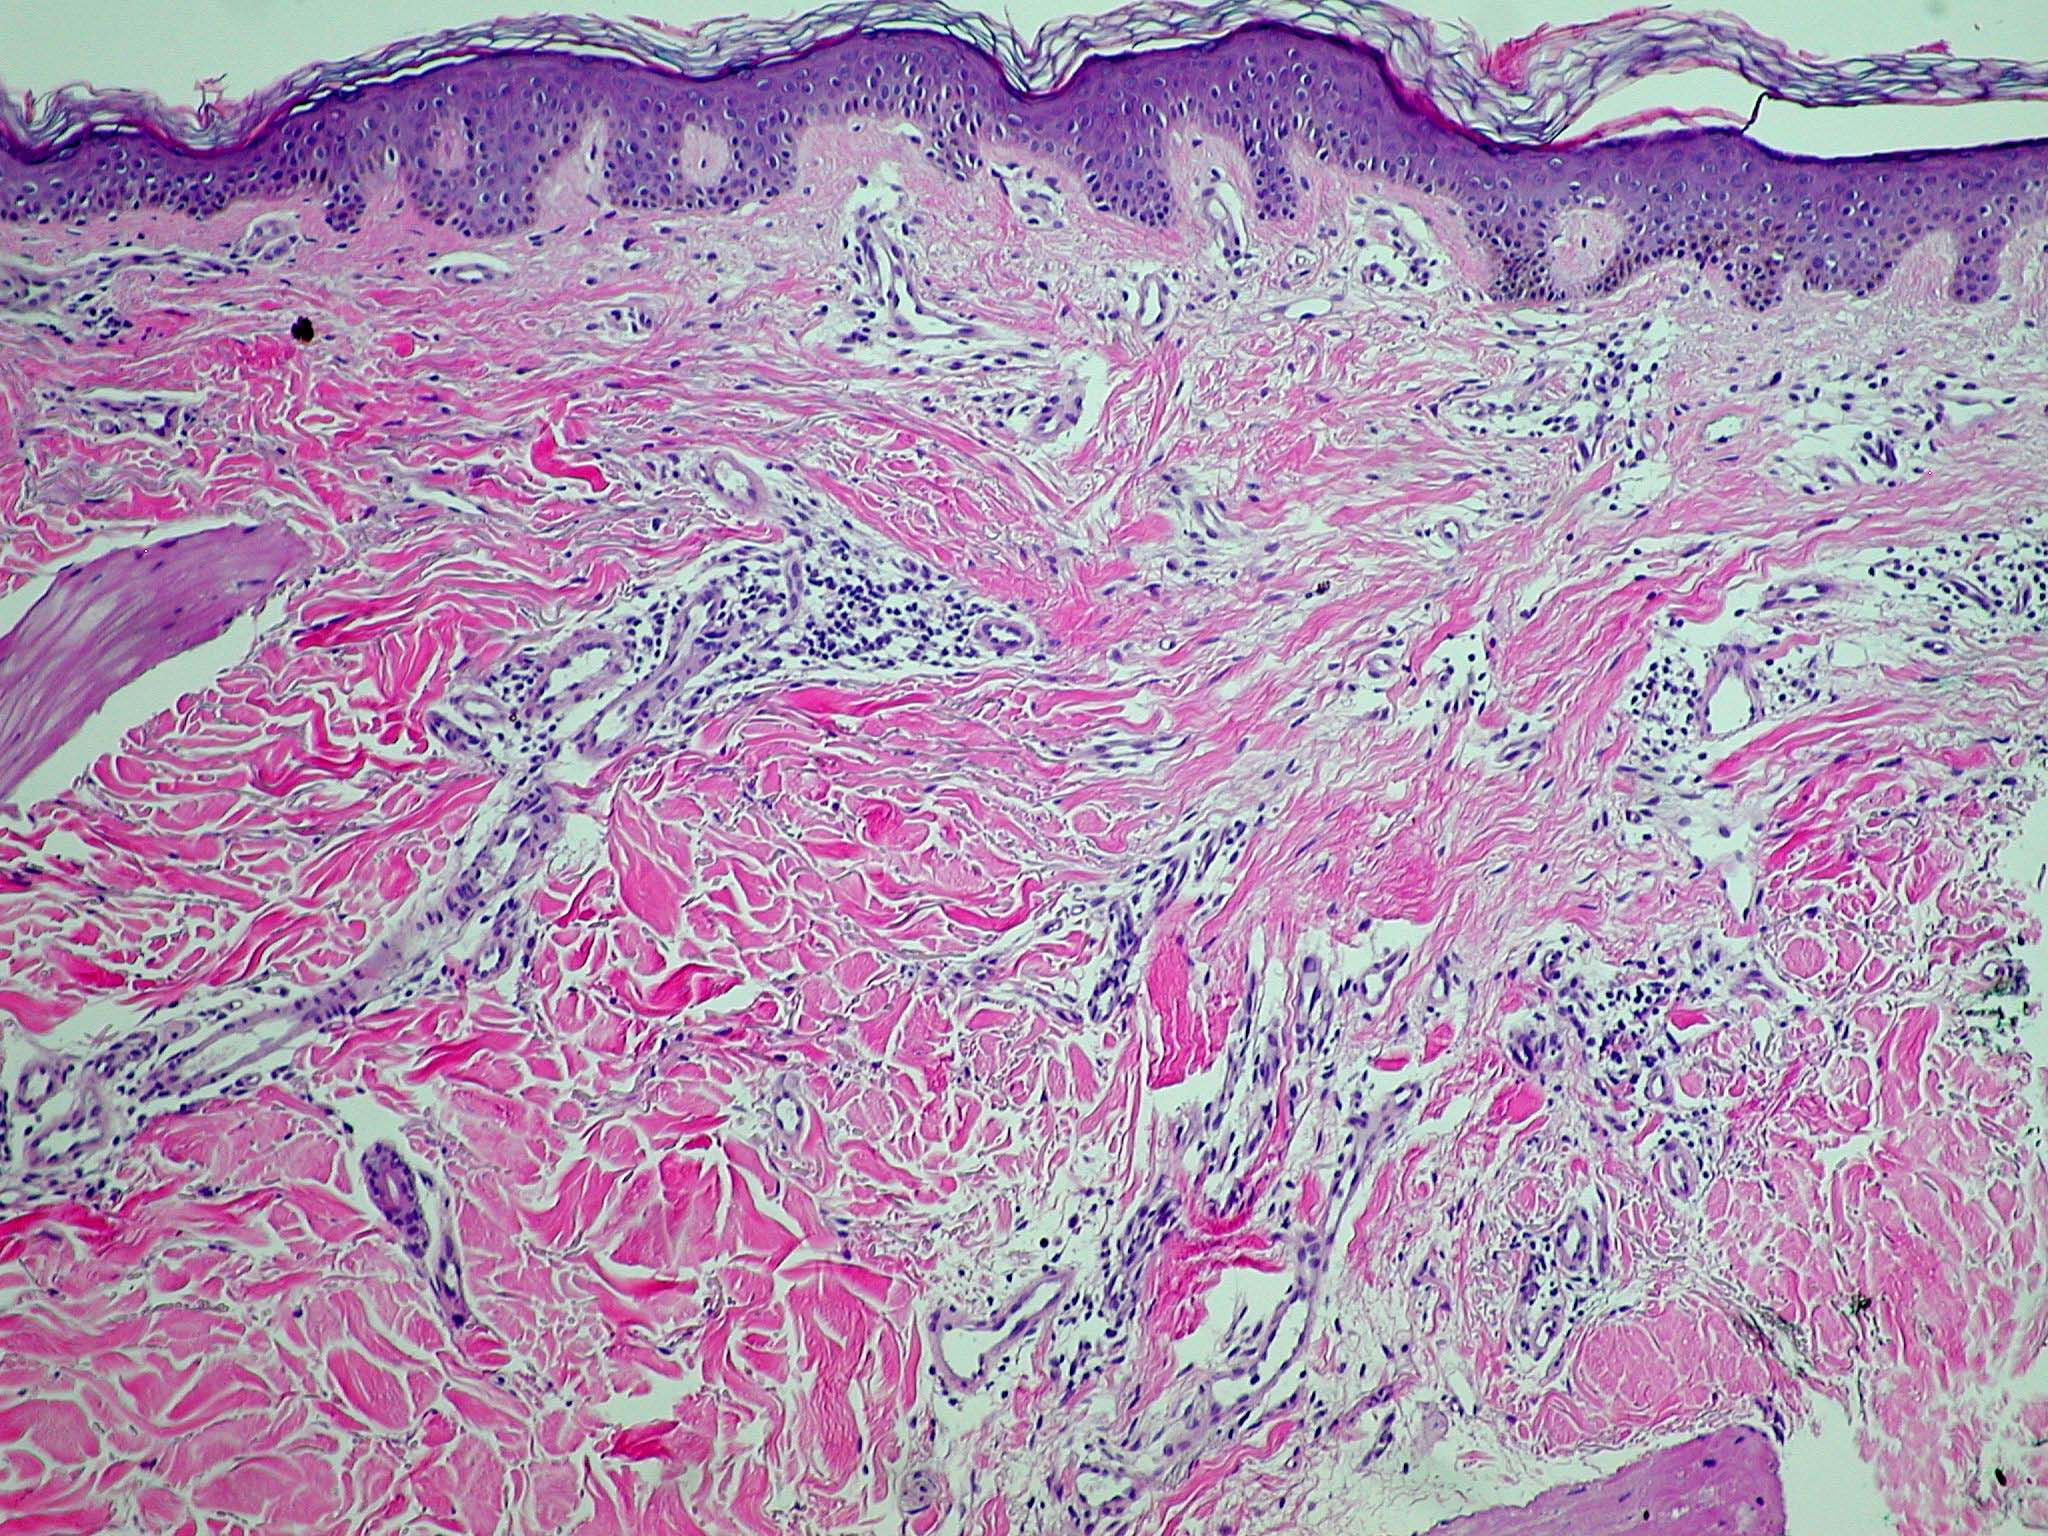

mastocytose